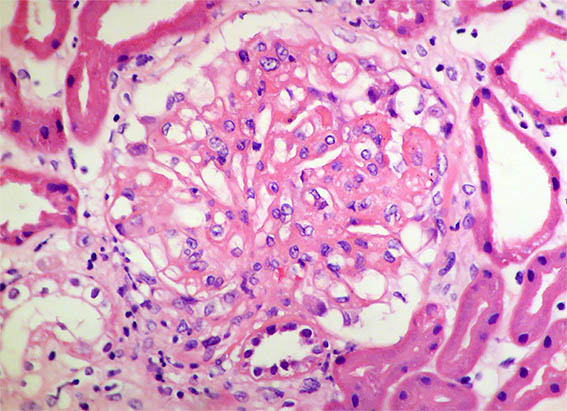

Figura 1. H&E, X400. Hipercelularidad segmentaria y engrosamiento de paredes capilares.